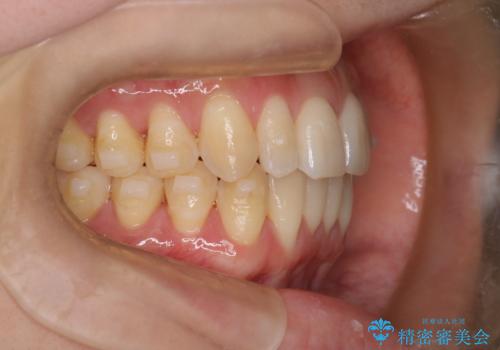

【インビザライン】反対咬合を治したい

- 前歯の反対咬合を主訴に来院されました。

インビザラインにて歯列弓の拡大により叢生の改善を行うことができ、患者様にも満足していただました。

前歯の反対咬合は歯牙への負担も大きくできるだけ早期に治療を行うことを推奨しています。